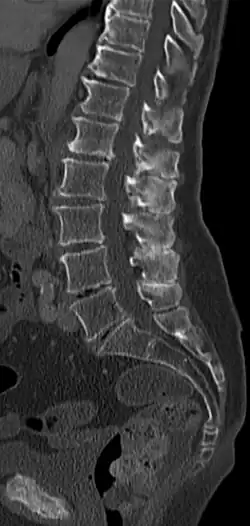

- Radiologisch: Radiologisch nachgewiesene Berührung von Dornfortsätzen, hauptsächlich im Bereich der Lendenwirbelsäule infolge verstärkter Lordosierung und meist verschleißbedingter Verschmälerung der Bandscheiben mit Ausbildung reaktiver Sklerosen und Nearthrosen. Funktionsaufnahmen in Reklination zeigen eventuell den direkten Kontakt betroffener Dornfortsätze.